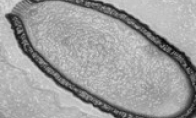

• 西伯利亚冻土发现史前巨型病毒:仍具有感染性

游戏新闻 2014-03-05 18:14:58

法国科学家在西伯利亚冻土发现史前巨型病毒这种史前病毒已经在俄罗斯西伯利亚地区的冻土层中封存了3万多年。俄罗斯西伯利亚地区法国国家科研中心与马赛大学的联合实验室当天发表新闻公报说,其科研团队从俄罗斯远东地区的楚科奇自治区采集到一份冻土样本,证实了“西伯利亚阔口罐病毒”(Pithovirus sibericum)的存在,其生存年代正是史前人类尼安德特人灭绝之时。这种巨型病毒直径超过0.5微米,可在光学显微镜下观察到,与其它两类超大型病毒有很大的不同,是目前人类已知的第三种超大型病毒。此前,科学家分别于2003年和2013年发现拟菌病毒(Mimivirus)和潘多拉病毒(Pandoravirus)。起初,这种形状像古代酒瓮(Pithos就是至指古希腊的一种陶罐)的病毒让专家以为它只是&ldqu